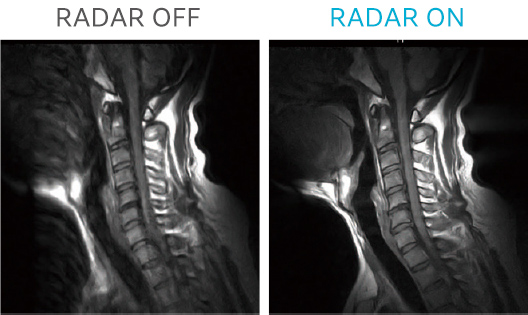

RADAR is a motion artifact reduction technique that fills k-space radially. RADAR GrE is now available on AIRIS Vento Plus.